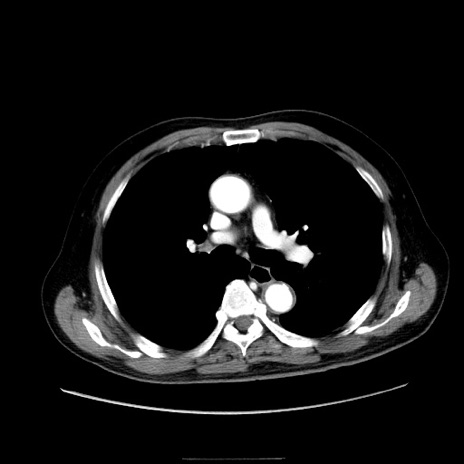

症例30(横断像)

【症例】80歳代男性

【主訴】臍周囲痛

【現病歴】約6時間前から臍下部痛が出現。次第に腹部膨隆・背部痛も生じてきたため来院。背部痛の場所は変化しない。

【身体所見】意識清明、BT 36.3℃、BP  131/87mmHg、P 87bpm、SpO2 100%(RA)、臍周囲自発痛・圧痛あり、反跳痛なし、自発痛部位に一致して板状硬あり、腹部膨隆、腸雑音減弱、CVA tenderness両側陰性。